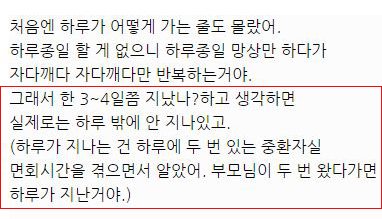

대단한 얘기는 아니지만 중환자실에 3주동안 무의식으로 있었던 썰 풀어볼게